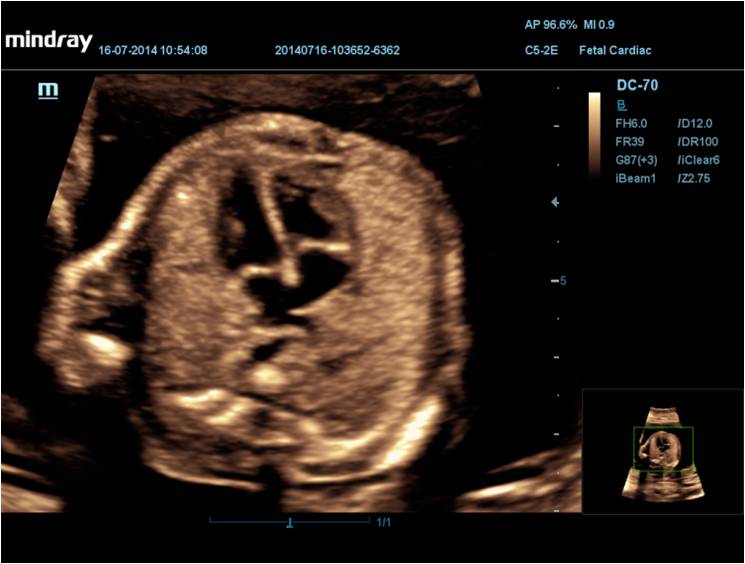

iLive Режим свето-теневой обработки объемного изображения с возможностью перемещения виртуального источника освещения. Имитируя несколько источников света переменной интенсивности, iLive помогает значительно улучшить анатомическое детальное разрешение как поверхности, так и внутренних структур за счет высокоскоростной объемной визуализации.